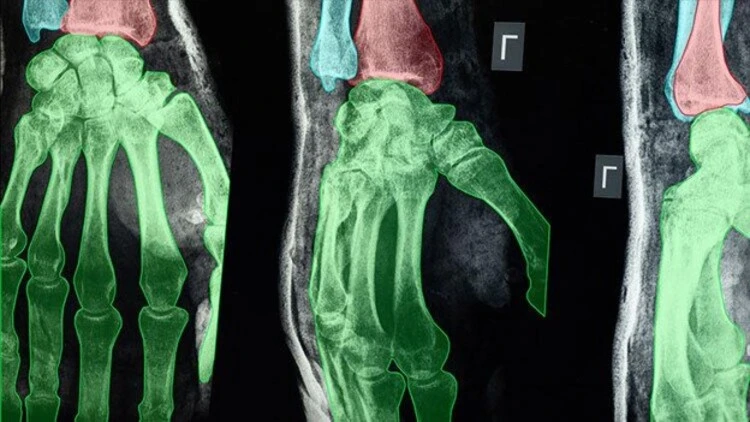

Radiology and Pathology

AI is transforming radiology. It enhances diagnostic accuracy by finding subtle patterns in medical images that the human eye may miss. This capability is crucial for early detection of conditions like neurological disorders, and cardiovascular diseases. For example, AI-enhanced SPECT imaging has been shown to improve the detection of coronary artery disease by generating images similar to those from more expensive hybrid scanners, reducing costs and time, while maintaining accuracy.

For instance, collecting high-quality X-ray, CT, and MRI data can be challenging. To overcome this, Keymakr collaborates with a network of local and overseas partners to build custom medical imaging datasets. The team is capable of classifying, validating, and preparing datasets for various medical diagnoses. If a company starts without a defined process, Keymakr can assist in developing a model that suits special requirements. It spans disease detection, surgical AI, pathology research, and other projects.

- Bounding Box: This tool marks areas of interest in medical images, such as identifying tumors in MRI or CT scans, and assists with initial screenings.

- Semantic Segmentation: This tool classifies each pixel in an image to identify specific anatomical structures or conditions, such as separating organs in radiological images. It is crucial for precise surgical planning.

- Keypoint Annotation: Useful for tasks like analyzing joint positions in musculoskeletal images or tracking anatomical landmarks in 3D scans. This tool helps in the assessment of movement disorders or surgical outcomes.